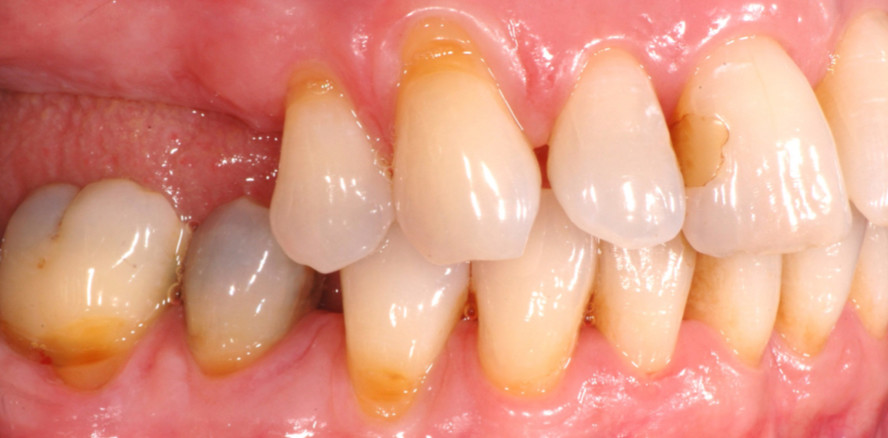

Ein 59-jähriger allgemeinmedizinisch gesunder Patient stellte sich mit dem Wunsch nach einer funktionellen Rehabilitation vor. Zum Zeitpunkt der Erstvorstellung lag eine parodontal kompromittierte Situation vor, die durch einen hohen konservierenden Restaurationsgrad flankiert wurde. Im Ober- und Unterkiefer lag ein horizontaler Knochenverlust von 50 bis 70 Prozent an den einwurzeligen und von 50 bis 80 Prozent an den mehrwurzeligen Zähnen vor. Die parodontale Situation der Molaren und Prämolaren wurde neben erhöhten Sondierungstiefen (ST) von Furkationsbeteiligungen (Grad II bis III) und Lockerungsgraden (II bis III) dominiert (Abb. 1 und 2). Anhand der neuen Klassifikation lag ein Parodontitis Stadium III, Grad B vor.1, 2

Zum Zeitpunkt der Behandlungsübernahme war die Patientin 57 Jahre alt. Aufgrund eines Herzinfarkts war sie seit fünf Jahren (nach ca. 25 Jahren) Nichtraucherin. Die Patientin war medikamentös mit einer dualen Thrombozytenaggregation (ASS, Clopidogrel) eingestellt. Grund der Vorstellung und ihr Hauptanliegen war neben dem Zahnerhalt eine festsitzende Versorgung der Freiendsituation. Zum Zeitpunkt der Erstvorstellung lag eine konservierend parodontal und prothetisch insuffizient versorgte Gebisssituation vor (Abb. 7).

Eine 51-jährige anamnestisch unauffällige Patientin stellte sich mit der Sorge vor einem spontanen Zahnverlust vor. Zu diesem Zeitpunkt lag eine konservierend und prothetisch insuffizient versorgte Gebisssituation vor. Eine Parodontitistherapie wurde bisher nicht durchgeführt. Die Patientin gab an, zeitlebens Nichtraucherin gewesen zu sein. Zahn 42, Grund der Vorstellung, wies einen Mobilitätsgrad III mit vertikaler Komponente auf. Zahn 46 zeigte ebenfalls einen Mobilitätsgrad III mit einer Furkationsbeteiligung Grad III. Die Reaktion auf den Kältetest fiel an beiden Zähnen negativ aus. Im Ausgangsbefund betrug der Anteil der ST von ≥ 6 mm 30 Prozent. Neben einer deutlich geröteten und ödematös geschwollenen Gingiva wiesen multiple Stellen (Regio 15, 26, 36, 42) Suppurationszeichen auf. Es konnten harte und weiche Beläge in supra- und subgingival-Bereichen identifiziert werden, die mit einer ausgeprägten parodontalen Entzündungssituation assoziiert waren (Abb. 11). Unter Verwendung der neuen Klassifikation von Parodontalerkrankungen lag eine Parodontitis Stadium III, Grad A vor.